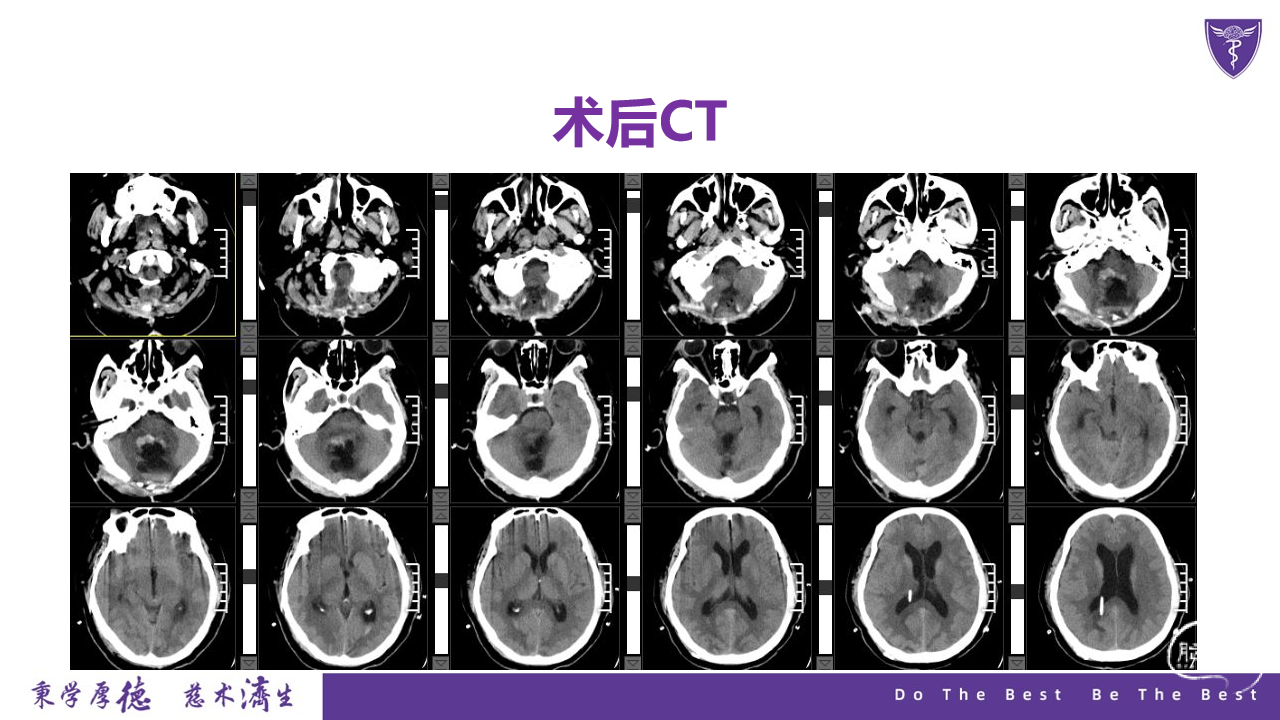

王杰教授团队:四脑室复发室管膜瘤切除术